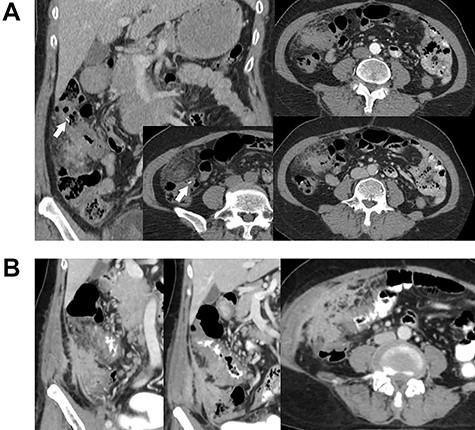

A 63-year-old female with no underlying disease presented with a palpable mass on the right side of her abdomen. Abdominal computed tomography (CT) was performed at the primary hospital and revealed colonic hepatic flexure thickening (Fig. 1A). Interestingly, imaging also revealed a foreign body-like object near the affected area. The clinical significance of the particle was unknown. Colonoscopy was then performed to the terminal ileum, and no abnormalities were identified. A 1-month repeat CT scan was planned, but the patient refused and was lost to follow-up. The patient returned 5 months later with an increase in the size of the palpable mass, anorexia, weight loss and chronic intermittent low-grade fever. There were no bowel habit changes. On physical examination, her temperature was ~38.1°C, and slightly pale conjunctivae were noted; lymphadenopathy was not present. An ill-defined, at least 10-cm diameter, fixed, intra-abdominal mass was palpated in the patient's right lower abdominal quadrant. Blood test results were essentially normal except for mild anemia.

Contrast-enhanced abdominal CT. Images (A) and (B) were obtained 5 months apart. Image A shows irregular circumferential thickening of the colonic hepatic flexure. An elongated foreign body is also visible in the area (arrow). Image B shows an increase in the size and extension of the thickening. There is also a newly-detected heterogenous enhancing mass-like lesion involving the lateral wall of the cecum and proximal ascending colon, with enhancement indicating irregular thickening of the adjacent peritoneum.

Repeat abdominal CT (Fig. 1B) revealed an increase in the size and extension of irregular circumferential thickening of the proximal transverse colon with a newly-detected heterogenous enhancing mass-like lesion involving the lateral wall of the cecum and proximal ascending colon. There was also irregular thickening enhancement of the adjacent peritoneum and right lower abdominal wall without other important organ invasion. The foreign body particles had disappeared. Cancer of the cecum was one of the differential diagnoses.